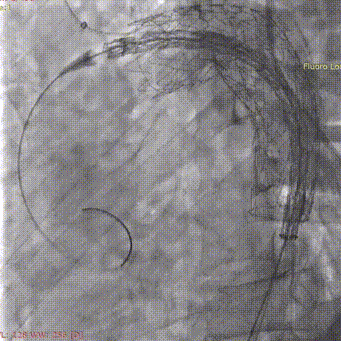

3. 右侧肱动脉置入斑马导丝,建立右肱动脉与股动脉之间工作轨道,沿加硬导丝及斑马导丝置入TBE主体支架(型号:TAC123715W)。调整机头角度,确认双导丝间无缠绕。

斑马导丝是治疗什么的「胸有乾坤」至简至易 行之有效—— Zone 0 TBE植入治疗弓部动脉瘤病例报道_https://www.jmylbn.com_新闻资讯_第16张

斑马导丝是治疗什么的「胸有乾坤」至简至易 行之有效—— Zone 0 TBE植入治疗弓部动脉瘤病例报道_https://www.jmylbn.com_新闻资讯_第17张